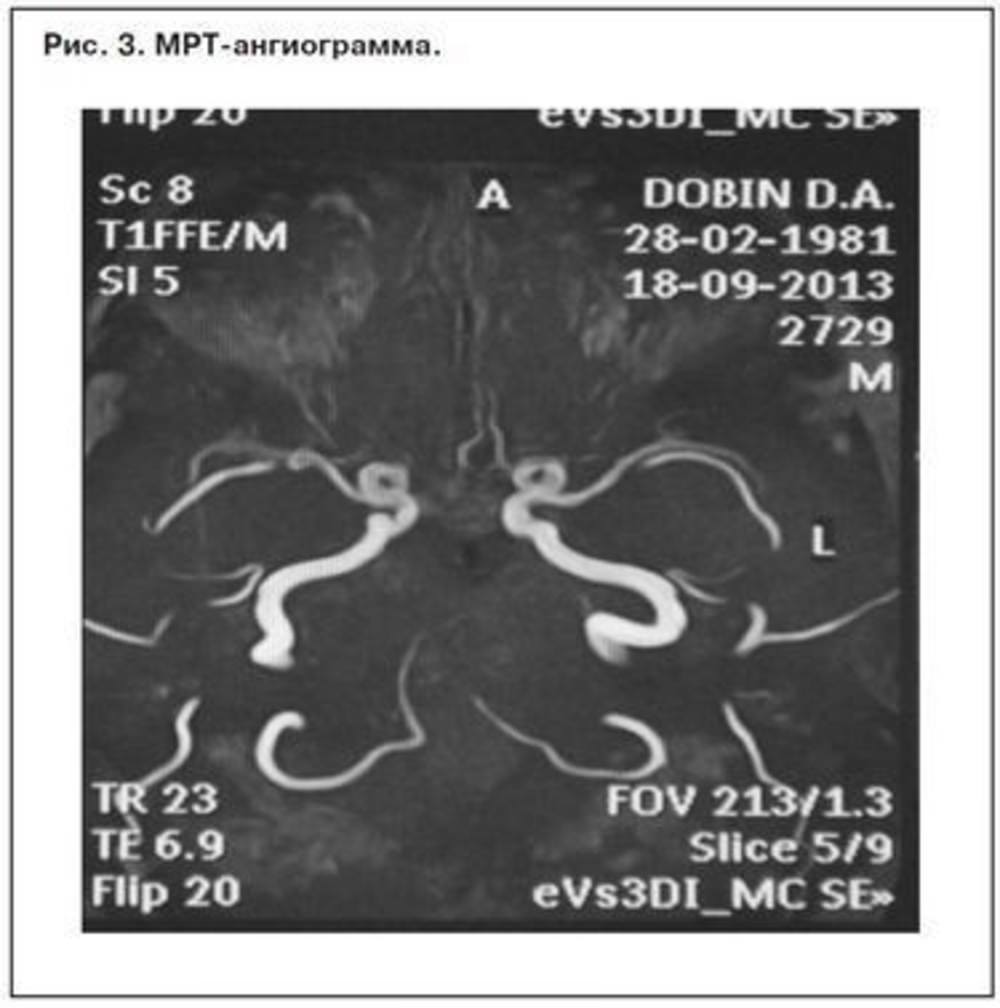

Выявленно значительное сужение просвета и снижение кровотока (снижение интенсивности МР-сигнала) по А1 сигменту правой передней мозговой артерии на всем видимом протяжении, кровоснабжение А2 и А3 сегментов правой ПМА осуществляется приемущественно из басейна левой ВСА — вариант полной передней трифуркации левой ВСА.

Заключение: МР данных на наличие изменений очагового и диффузного характера в веществе мозга не выявленно.Нерезко выраженная бивентрикулярная открытая гидроцефалия.

МРА картина варианта развития Виллизиева круга в виде неполной задней трифуркации правой ВСА, полной передней трифуркации левой ВСА.

МРА данных за наличие артерио-венозных мальформаций, аневризматицевкого расширения интрактариальных артерий не выявленно.